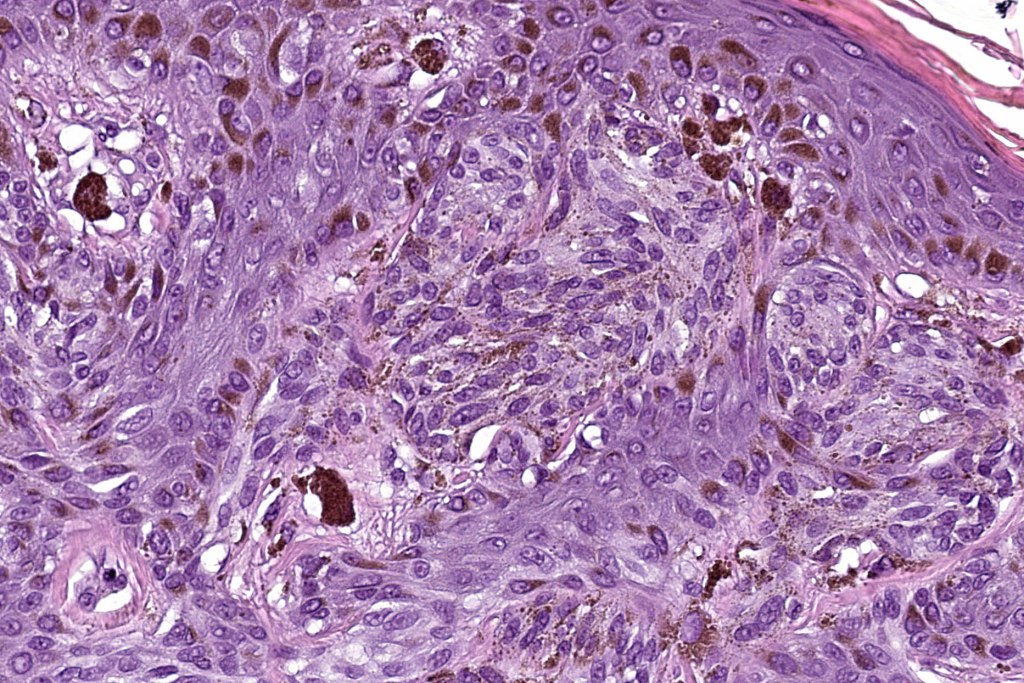

•Vertically orientated oval junctional nests

. Heavy pigmentation although hypopigmented/amelanotic varinats can be encountered

•Spindle cells with small nucleoli

•Mild pleomorphism

•Kamino bodies

•Central focal Pagetoid spread & elimination of nests sometimes seen

•Adnexal involvement